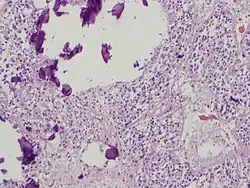

The pineal body in humans consists of a lobular parenchyma of pinealocytes surrounded by connective tissue spaces. The gland's surface is covered by a pial capsule.

The pineal gland consists mainly of pinealocytes, but four other cell types have been identified. As it is quite cellular (in relation to the cortex and white matter), it may be mistaken for a neoplasm.[18]

Tumors

Tumors of the pineal gland are called pinealomas. These tumors are rare and 50% to 70% are germinomas that arise from sequestered embryonic germ cells. Histologically they are similar to testicular seminomas and ovarian dysgerminomas.[39]

A pineal tumor can compress the superior colliculi and pretectal area of the dorsal midbrain, producing Parinaud's syndrome. Pineal tumors also can cause compression of the cerebral aqueduct, resulting in a noncommunicating hydrocephalus. Other manifestations are the consequence of their pressure effects and consist of visual disturbances, headache, mental deterioration, and sometimes dementia-like behaviour.[40]

These neoplasms are divided into three categories: pineoblastomas, pineocytomas, and mixed tumors, based on their level of differentiation, which, in turn, correlates with their neoplastic aggressiveness.[41] The clinical course of patients with pineocytomas is prolonged, averaging up to several years.[42] The position of these tumors makes them difficult to remove surgically.